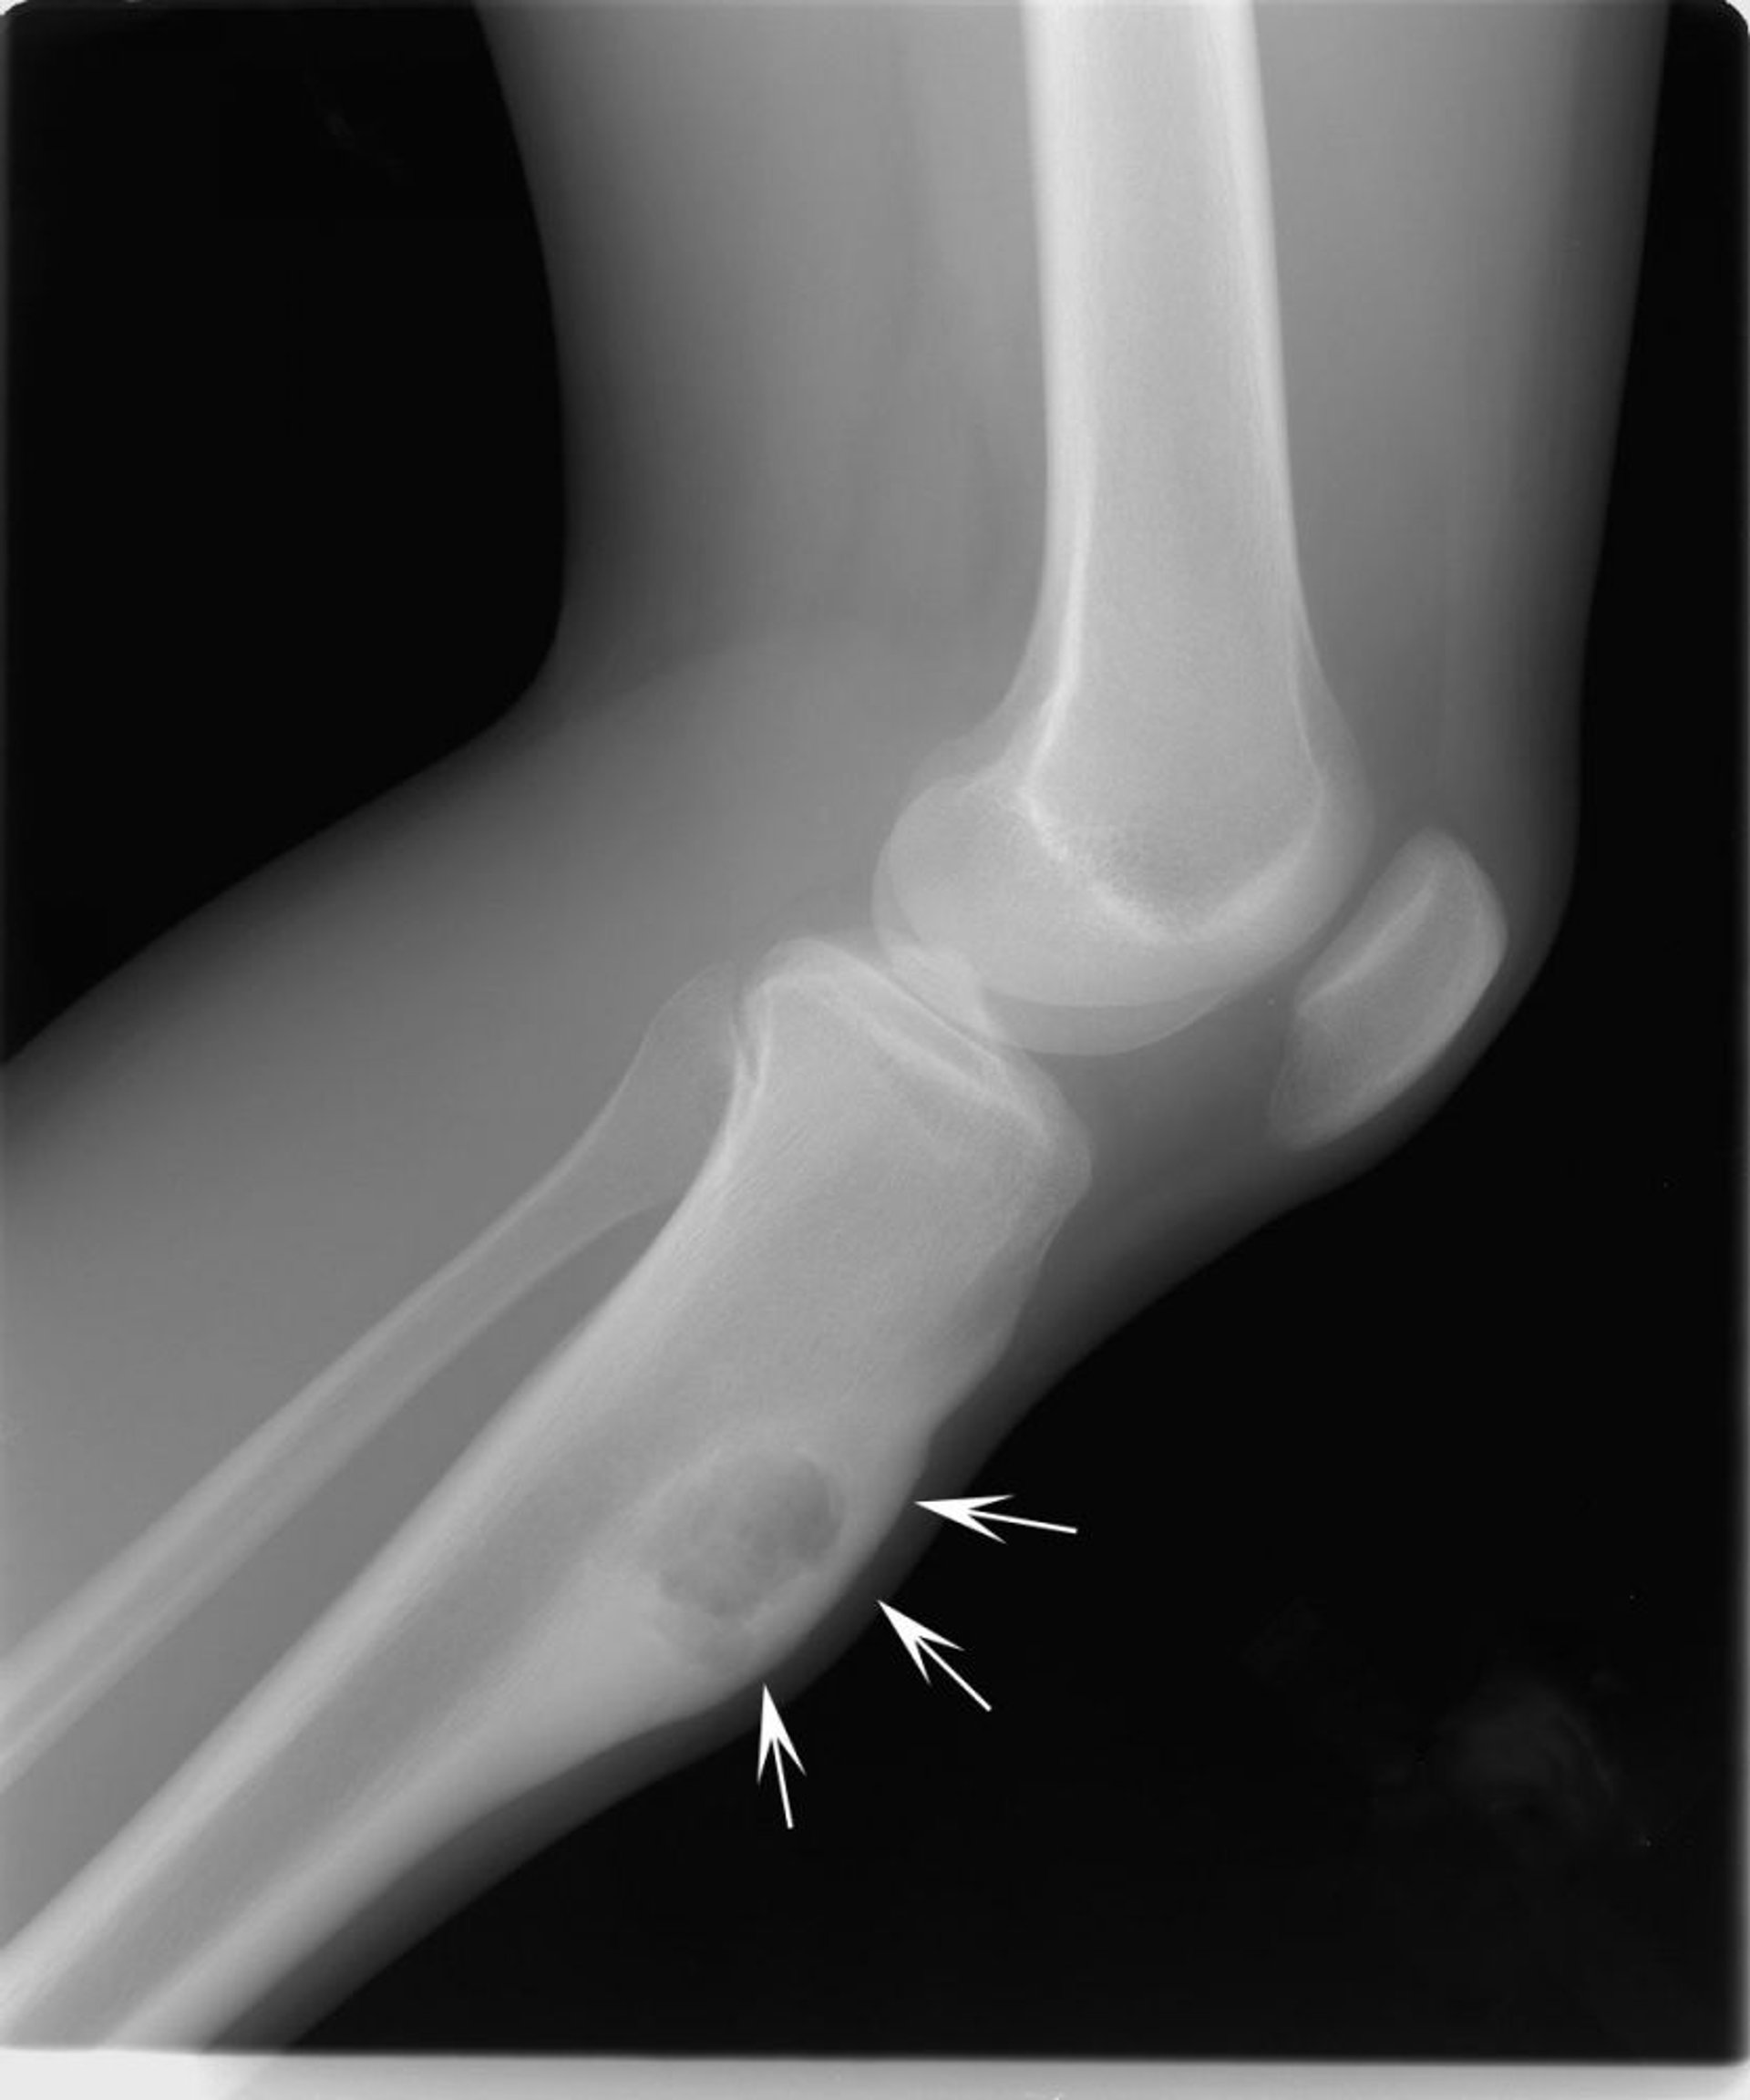

この膝のX線写真には、膝の下のすねの骨に生じた軟骨粘液線維腫(矢印)が写っています。

Image courtesy of Michael J.Joyce, MD, and Hakan Ilaslan, MD.